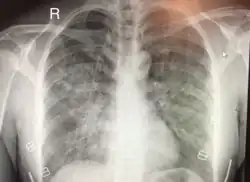

| Chest x-ray of HAPE showing characteristic patchy alveolar infiltrates with right middle lobe predominance. | |

On physical exam, increased breathing rates, increased heart rates, and a low-grade fever 38.5o C (101.3o F) are common.[9][3] Listening to the lungs may reveal crackles in one or both lungs, often starting in the right middle lobe.[9][3] Imaging studies such as X-ray and CT imaging of the chest may reveal thoracic infiltrates that can be seen as opaque patches.[14][9][3] One distinct feature of HAPE is that pulse oximetry saturation levels (SpO2) are often decreased from what would be expected for the altitude. People typically do not appear as ill as SpO2 and chest X-ray films would suggest.[9][3] Giving extra oxygen rapidly improves symptoms and SpO2 values; in the setting of infiltrative changes on chest X-ray, this is nearly pathognomonic for HAPE.[3]

Hypoxic pulmonary vasoconstriction (HPV) occurs diffusely, leading to arterial vasoconstriction in all areas of the lung. This is evidenced by the appearance of "diffuse," "fluffy," and "patchy" infiltrates described on imaging studies of climbers with known HAPE.[9]